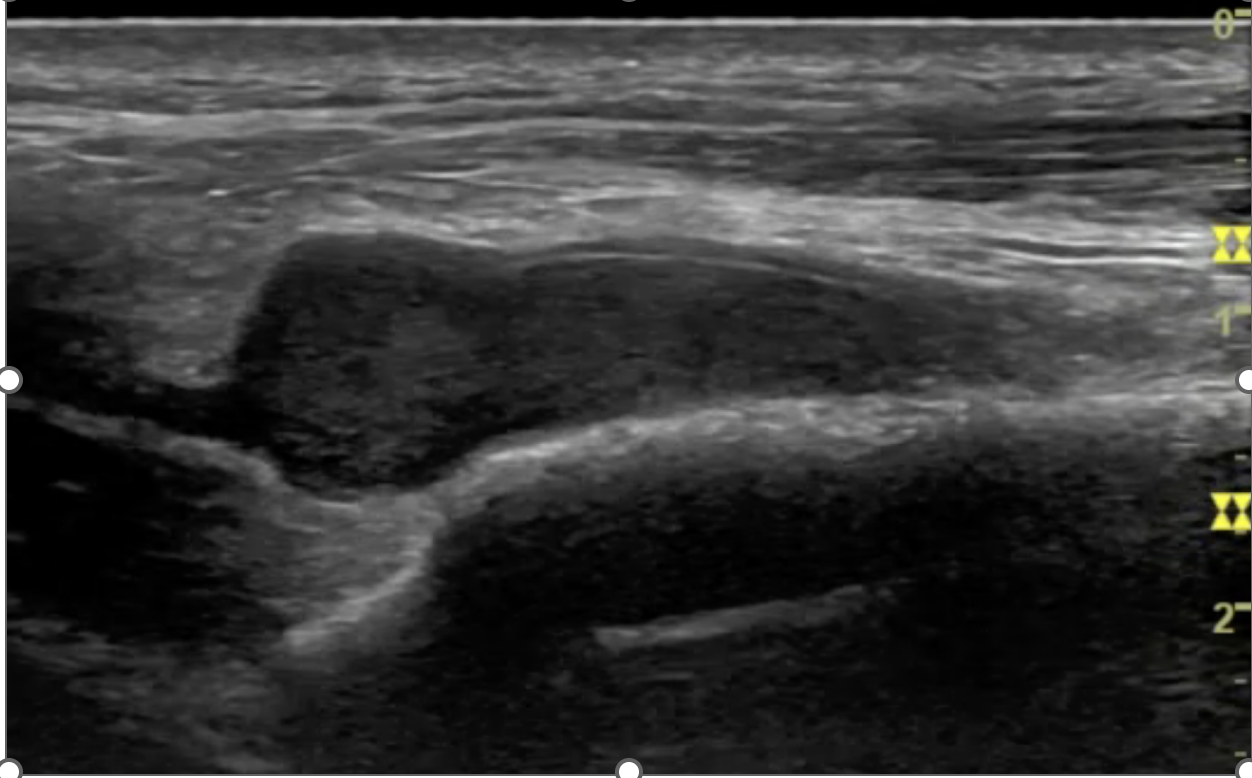

Image Interpretation: LAX view, ill-defined mass abutting the anterior tibial artery between the tibialis anterior and extensor hallucis longus tendons. 2.7 x 0.8 x 1.1 cm. Notable blood flow proximally and within mass observed with Doppler.

Teaching Pearl: Glomus tumors typically present in the upper extremities (particularly the hand/fingers) and as such can often be difficult to diagnose in other parts of the body. Patients with glomus tumors often have pinpoint tenderness, paroxysmal pain, and cold sensitivity. Clinical diagnosis can be tricky as those three characteristics are often isolated and less frequently occur together. US/MRI are the diagnostic imaging modalities of choice. US with doppler can be helpful in diagnosis as they can be mistaken for other benign masses and can help assist in the evaluation of an arterial supply feeding the tumor. A case series from the Hospital for Special Surgery (HSS) over the course of 18 years excised 11 glomus tumors from the foot, with the majority of them located in the distal hallux.1 The glomus tumor from this case matches descriptions of other extradigital glomus tumors, including a "vascular stack", however it is larger in size compared to the mean size (1 cm) from a study analyzing non-subungal glomus tumors.2 Typical glomus tumors are visualized as small, well-circumscribed, hypoechoic nodule with prominent arterial flow (vascular stalk).